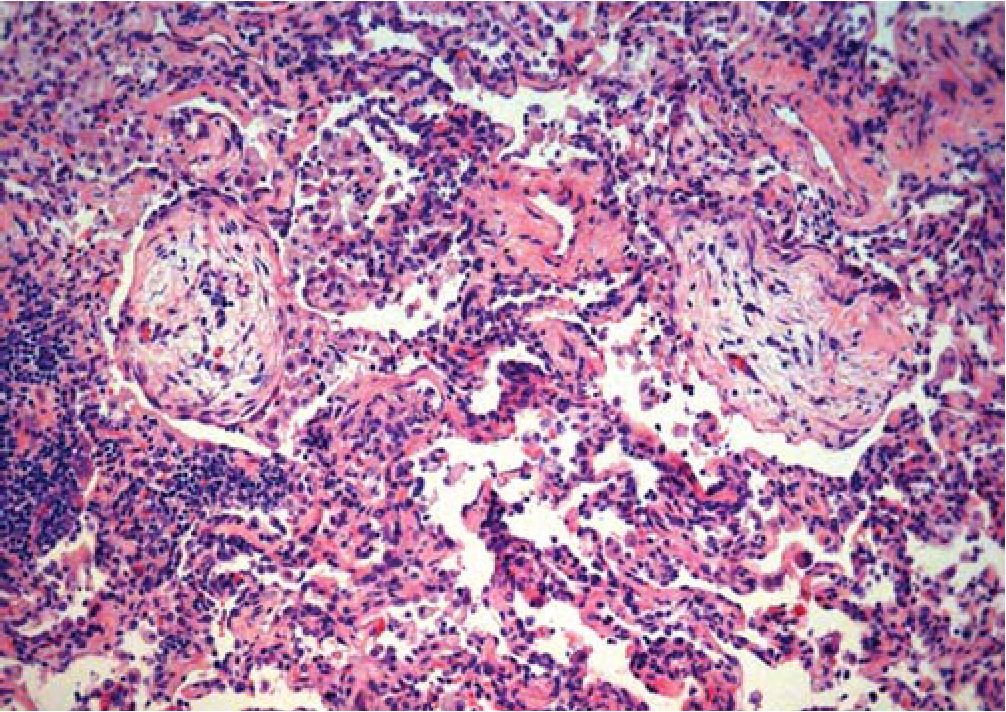

Рис. 2. Грануляционная ткань в просвете респираторной бронхиолы и альвеолярном ходе.

Окраска гематоксилином и эозином. X 40

Рис. 3. Грануляционная ткань в альвеолярном ходе в сочетании с небольшим скоплением макрофагов, деформация ткани легкого.

Окраска гематоксилином и эозином. X100

Ткань легкого деформирована за счет врастания в полости альвеол и просветы части респираторных бронхиол 1-го порядка грануляционной ткани в виде полипов (рис. 2), в части полостей альвеол - скопления макрофагов с примесью эозинофилов (рис. 3) и эритроцитов с единичными эозинофилами, в других просветах альвеол - скопление фибрина с примесью эозинофилов и нейтрофилов, отдельные стенки альвеол несколько утолщена за счет небольшой лимфоцитарной инфильтрации и пролиферации альвеолоцитов 2-го типа. Фиброэластоз стенок мелких ветвей легочной артерии с сужением просветов (рис. 4).

Стенки отдельных мелких сосудов слабо инфильтрированы лимфоцитами и эозинофилами, пролиферация эндотелиальных клеток.

Периваскулярные лимфоцитарные инфильтраты с примесью эозинофилов (рис. 5).

Облитерирующий респираторный бронхиолит с организующейся пневмонией. Фиброэластоз стенок артериол с очаговым сужением просветов. Очаговый подострый васкулит мелких сосудов.

Криптогенная организующаяся пневмония - это клиническое понятие относится к категории интерстициальных заболеваний легких, одной из разновидностей идиопатических интерстициальных пневмоний. Морфологическим субстратом данной патологии является облитерирующий бронхиолит с организующейся пневмонией (ОБОП), характеризующийся организацией экссудата и фибробластической реакцией в виде врастания грануляционной ткани в респираторные бронхиолы, альвеолярные ходы и альвеолы [ 1].